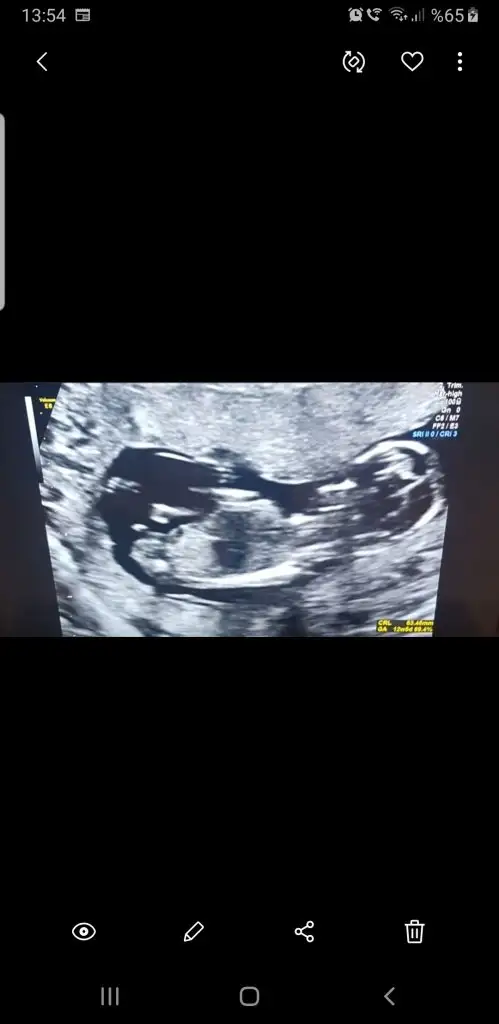

Pazartesi 13 haftalık olacağım o zaman tekrar atayım başka doktora gideceğim onun tahminini de yazarım. İnşallah kızdır 🙈🙈🙈 Aslında ikiz hamileydim çift yumurta biri kız birisi erkek oluyorlar genellikle. Kesemin birinde plesanta oluştu bebek gelişmedi. Hangisi daha güçlüydü o yönden de merak var hala aynı boyda iki kesem var çok üzücü.

Burada da karşıya bakıyor tam paralel değil dikte değil üsteki USG ile ayni nub gibi oyum kız gibi diyorum olursa 13+ paylaşın 🙈